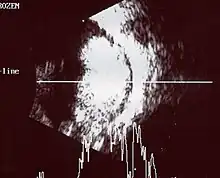

Traditional ultrasound B scan can detect calcifications in the tumour while high-frequency ultrasound B scan is able to provide higher resolution than the traditional ultrasound and determine the proximity of the tumour with front portion of the eye. MRI scan can detect high-risk features such as optic nerve invasion; choroidal invasion, scleral invasion, and intracranial invasion. CT scan is generally avoided because radiation can stimulate the formation of more eye tumours in those with RB1 genetic mutation.[24]

An ocular ultrasound of a large retinoblastoma tumor within the eye of a 3-year-old boy